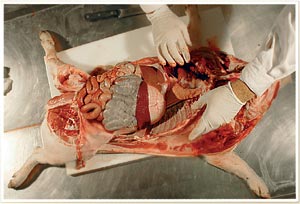

Atrophie séreuse de la graisse

Gélatinisation de la graisse due à la mobilisation des graisses de réserve par un animal qui perd du poids. C'est une observation courante sur des animaux atteints de la MAP qui ne meurent pas en phase aiguë ou subaiguë. Ils évoluent vers une maladie chronique.

Atrophie hépatique / hépatomégalie

Conséquence occasionnelle ou très occasionnelle de l'infection par le PCV2 sur des animaux qui développent cliniquement une MAP et qui présentent un ictère, et par conséquent une coloration orangée de la graisse. Cela correspond systématiquement à une inflammation (hépatite) grave du foie.